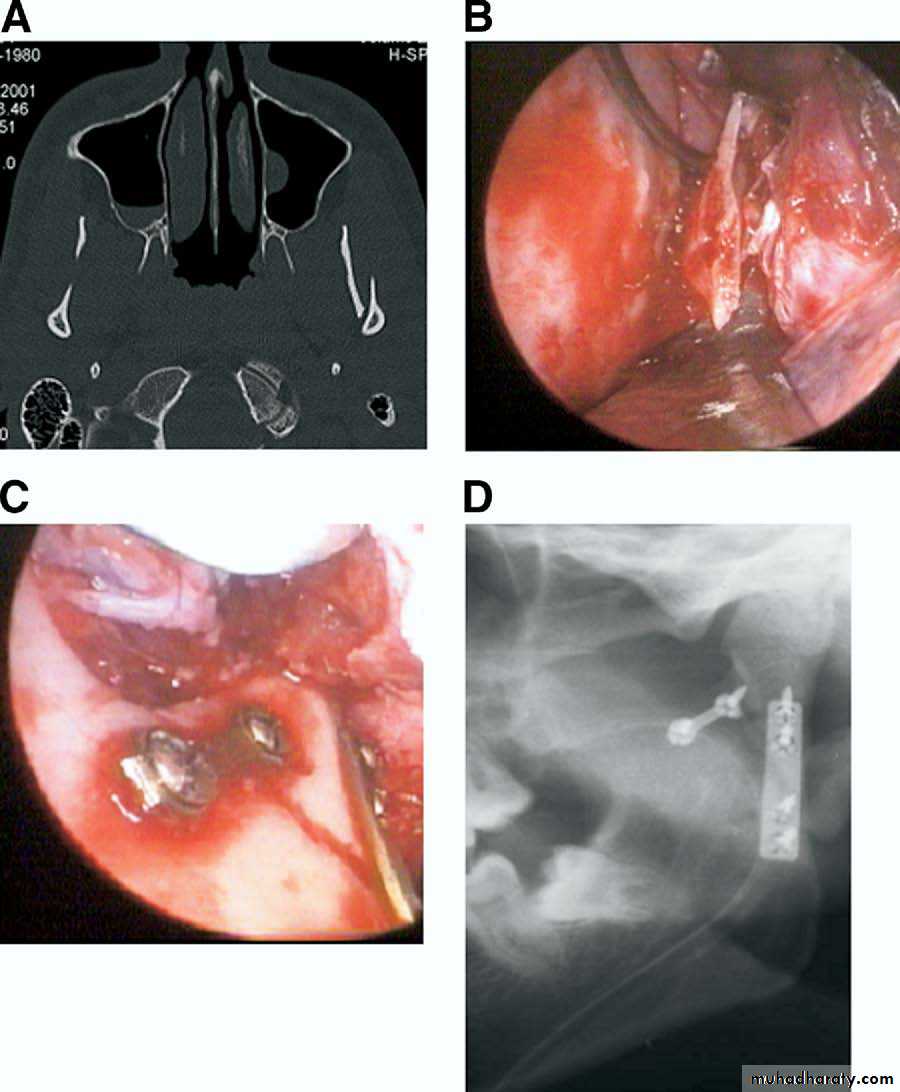

* Endoscopic reduction

The endoscopically assisted approach for open reduction and miniplate fixation of condylar mandibular fractures is a technique that allows fracture treatment with a limited transoral incision. Using an endoscope, superior visibility in areas of limited exposure can be obtained. In conjunction with the transoral approach, the scars are invisible, the risk of facial nerve damage is minimal, and, with subperiosteal preparation, the masseter muscle is not dissected. However, the procedure can be time-consuming. A steep learning curve for this technique has been reported.Open or closed ??